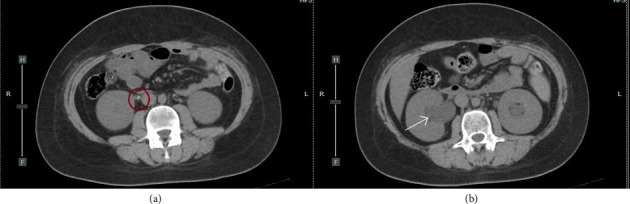

糖尿病酮症酸中毒(DKA)是儿童1型糖尿病(T1DM)的常见初始表现,发生率高达40%。DKA也可能与严重的并发症相关,包括肾结石。我们提出了一个12岁零8个月大的男孩谁发展急性肾损伤(AKI)继发于双侧尿路结石T1DM与DKA发病期间。在DKA的常规治疗后,实验室检查显示肌酐和氮血症升高。24小时后,患者出现腰痛和无尿。平片、超音波及电脑断层扫描显示双侧肾结石及盆腔扩张。我们进行了紧急双侧上升肾盂造影和支架置入。右侧输尿管支架置入成功,但左侧输尿管支架置入失败,原因是输尿管内解剖变异;因此,进行了肾造口术。利尿立即恢复,随后几天肾功能恢复正常,无永久性损害。据我们所知,这是第一例小儿DKA患者双侧结石合并输尿管狭窄的报道。对于严重DKA患者,我们建议在出现肌酐、少尿/无尿或腰痛异常升高时,采用低阈值的CT成像常规监测肾功能。早期多学科干预可迅速缓解肾后梗阻,预防永久性肾损害,改善预后。

Diabetic ketoacidosis (DKA) is a common initial presentation of type 1 diabetes mellitus (T1DM) in children occurring in up to 40% of cases. DKA can also be associated with severe complications, including nephrolithiasis. We present the case of a 12 years and 8-month-old boy who developed acute kidney injury (AKI) secondary to bilateral urinary lithiasis during the onset of T1DM with DKA. After conventional treatment for DKA, laboratory tests showed increased creatinine and azotemia. 24 hours later, he developed lumbar pain and anuria. Plain radiography, ultrasonography, and computed tomography (CT) revealed bilateral renal calculi and pelvic dilation. An urgent bilateral ascending pyelography with stent placement was performed. Right ureteral stenting was successful, but left stenting failed due to an intramural ureteral anatomical variant; thus, a nephrostomy was performed. Diuresis resumed immediately, and renal function normalized over the following days without permanent impairment. To our knowledge, this is the first reported case of bilateral lithiasis with ureteral stenosis in a pediatric patient with DKA. In patients with severe DKA, we recommend routine monitoring of kidney function with a low threshold for CT imaging whenever there is an unexpected rise in creatinine, oliguria/anuria, or lumbar pain. Early multidisciplinary intervention can promptly relieve postrenal obstruction, prevent permanent renal damage, and improve outcomes.